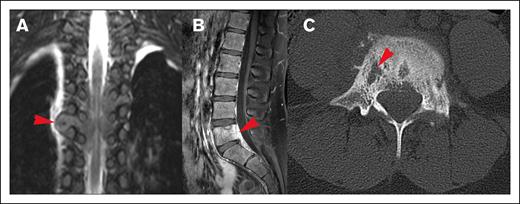

Figure 3.

Different origins of CNS HL lesions. (A) Tumor originating from bone (vertebral body of T12, L1, and L2). (B) Unclear tumor origin but very likely bone, with circumferential involvement and an associated soft tissue component. (C) Paravertebral tumor mass of the upper thoracic spine infiltrating through the right neuroforamen, demonstrated by the red arrow, likely originating from soft tissue.

Most lesions (92.7%) extended through the neural foramina of either the vertebrae or sacral bone; 2 lesions did not extend through the neural foramina, and 2 lesions could not be evaluated (Figure 4). Thirty-one lesions entered the spinal canal. Of these, 54.8% caused displacement of the spinal cord, 25.8% were adjacent to the spinal cord but did not cause displacement, and 19.4% did not contact the spinal cord (Figure 5). None of the lesions infiltrated into the spinal cord itself. Spinal cord edema was evaluated for patients who had MRI available (17 of 31 lesions). Among these evaluable lesions, only 12.9% had evidence of spinal cord edema.